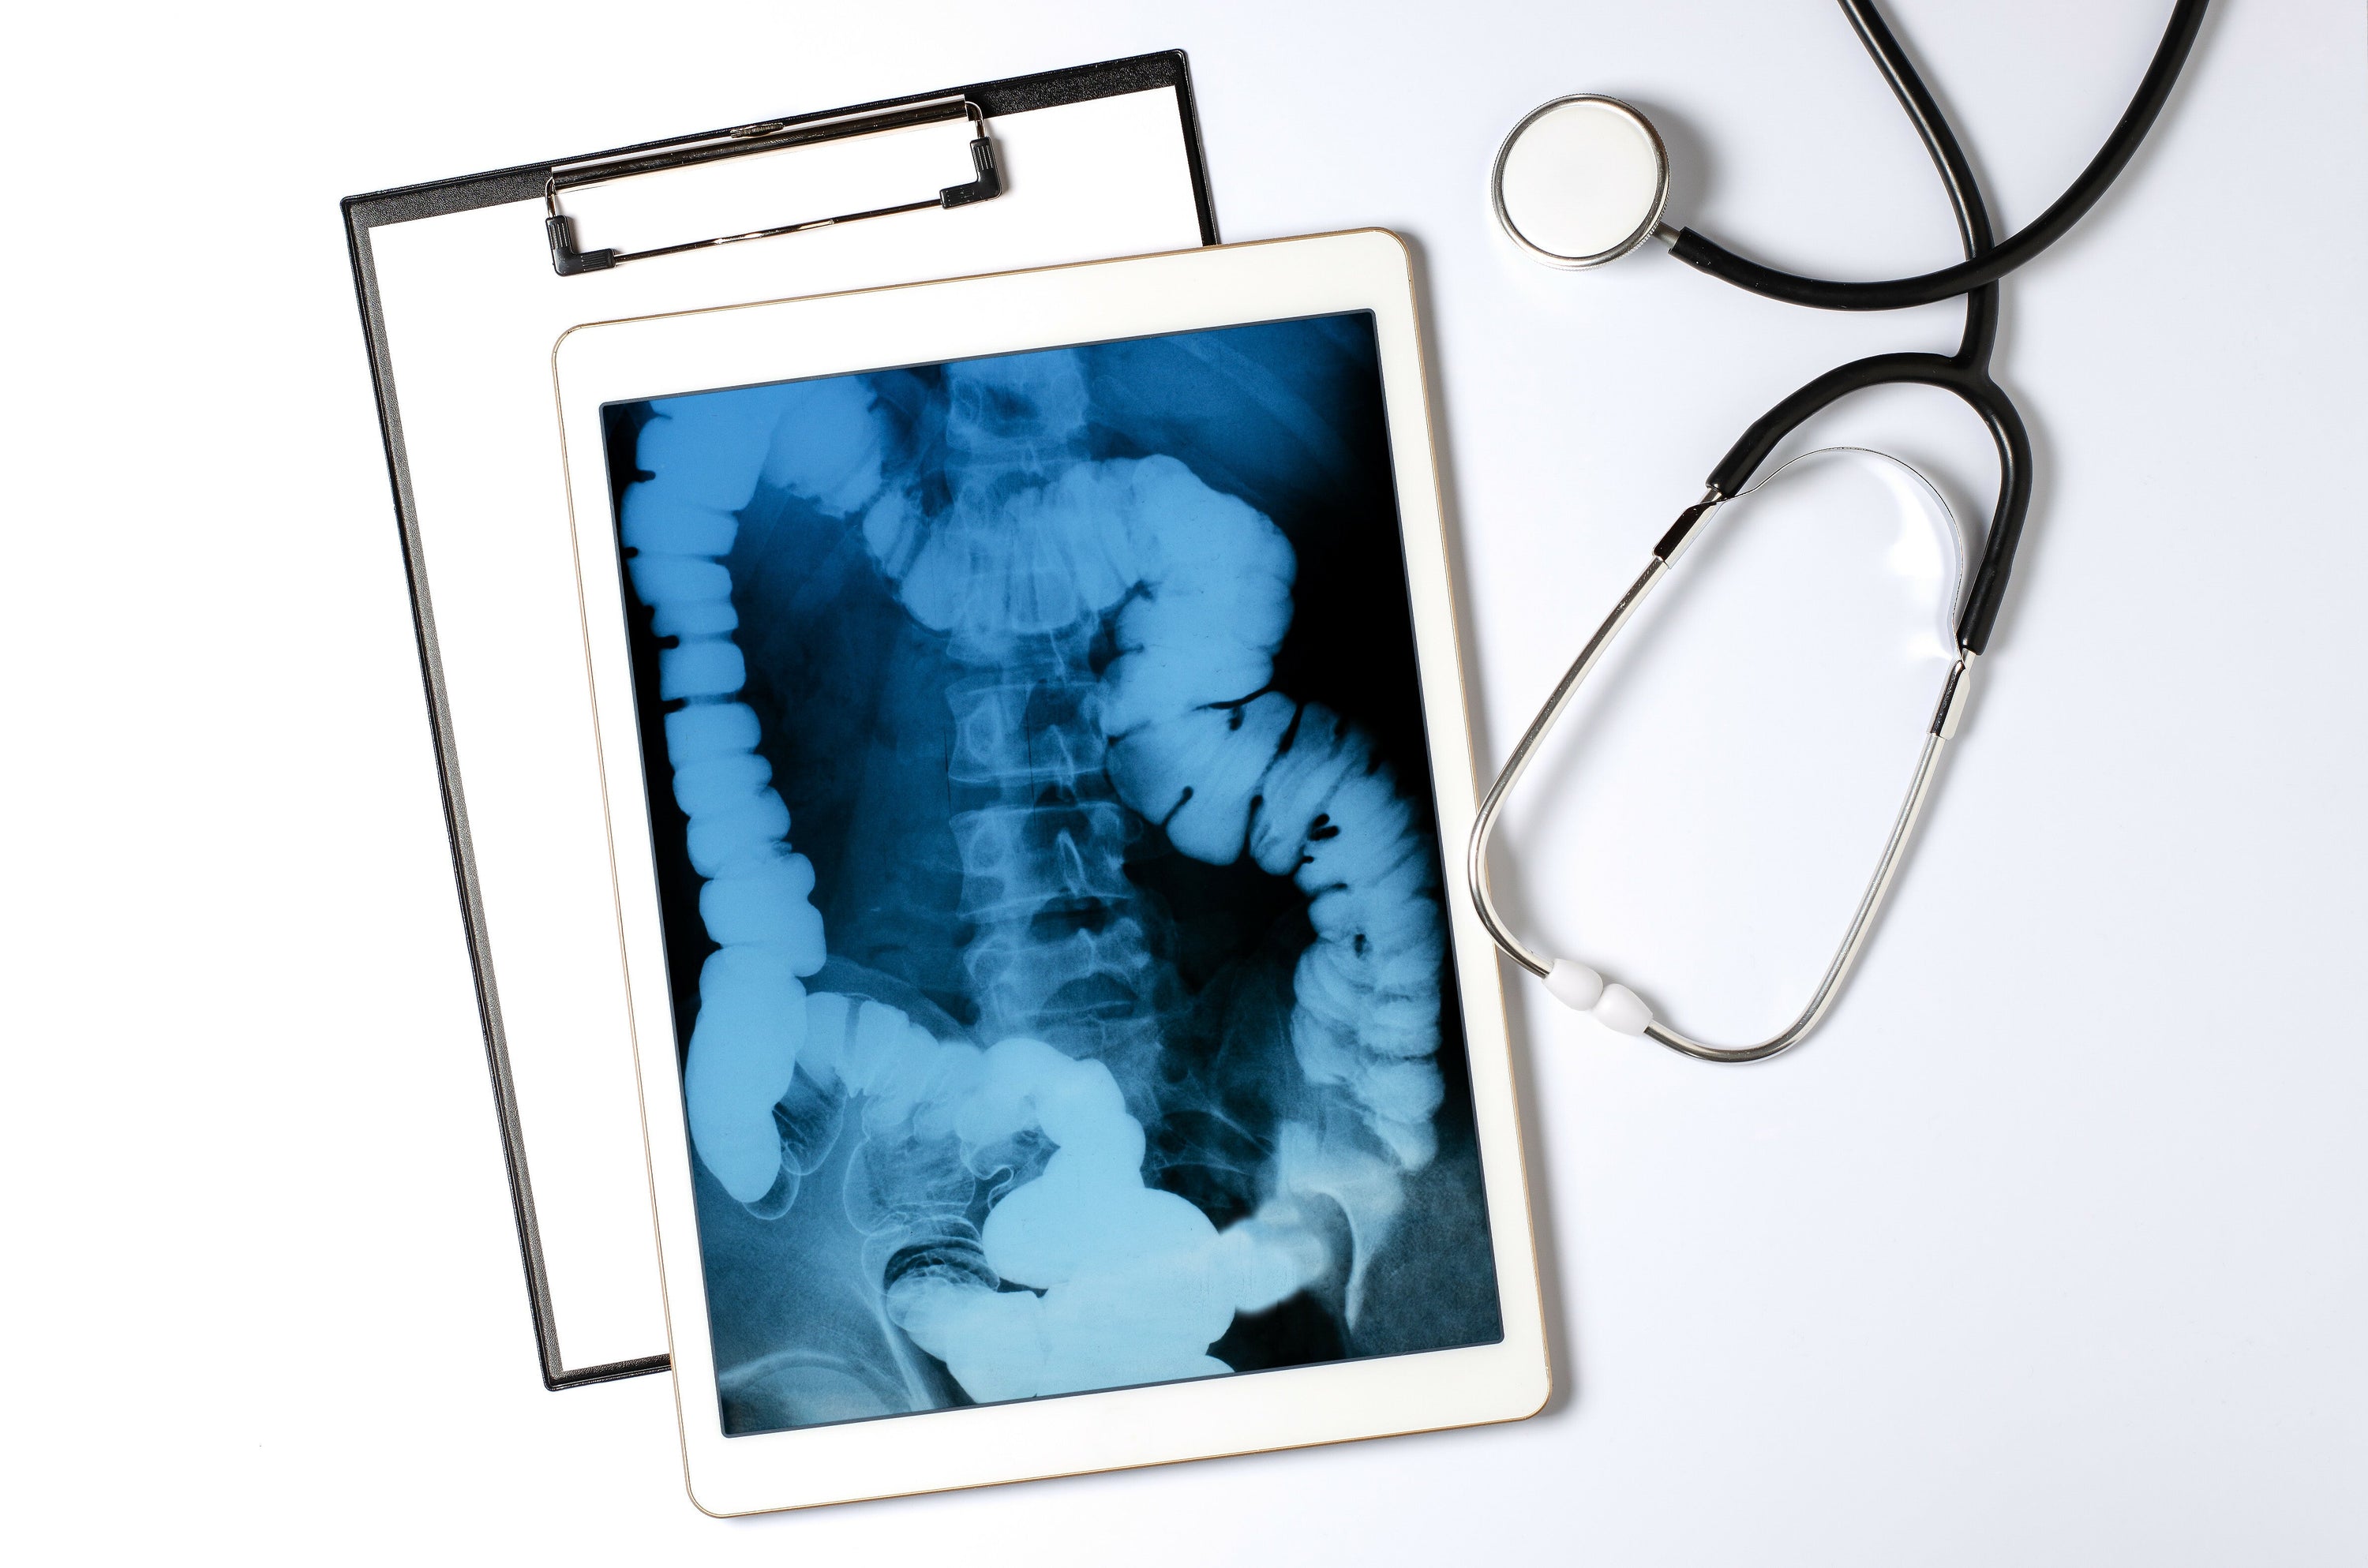

Die Funktion eines Röntgengeräts ist eine Abbildung von etwas, das unterhalb einer undurchsichtigen Oberfläche liegt. Bei einem klassischen Röntgengerät in der Medizin handelt es sich im Wesentlichen um eine Röhre, die Elektronen auf ein Metallstück schießt. Beim Aufprall der Elektronen entstehen dann Röntgenstrahlen, die durch den zu untersuchenden Körper geleitet werden. Da verschiedene Materialien die Strahlen unterschiedlich absorbieren, entsteht ein Bild auf einem sogenannten Detektor oder einer Fotoplatte. Dabei werden die Knochen in Weiß, weiches Gewebe in Grautönen und die Luft schwarz abgebildet. Heutzutage sind digitale Röntgentechniken in der Lage, diese Strahlen direkt in Bilder umzuwandeln, die auf einem Bildschirm angezeigt werden. Diese Modernisierung ermöglicht was eine sofortige Beurteilung der Bildgebung durch den Mediziner.

Erstaunlich an Röntgenbildern ist, wie sie die verborgenen Strukturen unseres Körpers offenbaren. Sie ermöglichen es Ärzten, Knochenbrüche zu diagnostizieren, Fremdkörper zu lokalisieren oder die Gesundheit von Gelenken zu beurteilen. Röntgenaufnahmen sind dabei nicht nur auf den menschlichen Körper beschränkt. Auch Einblicke in die Anatomie von Tieren sind mit der Röntgen-Technik möglich, was für veterinärmedizinische Diagnosen unerlässlich ist. Röntgen-Bildgebungen sind nicht nur für medizinisches Fachpersonal von Interesse, sondern faszinieren auch die Allgemeinheit, da sie etwas sichtbar macht, was für das bloße Auge nicht erkennbar ist.

Röntgenaufnahmen sind oft der erste Schritt im diagnostischen Prozess. Ohne diese kann oftmals nur eine Vermutung über einen vorliegenden Bruch angestellt werden. Die Anatomie-Bilder einer solchen Aufnahme können Aufschluss über Zustände geben, die durch äußere Untersuchungsmethoden nicht feststellbar sind. Dazu zählen etwa das Vorhandensein von Tumoren, das Ausmaß einer Infektion, das Vorliegen einer Knochenverletzung oder das Stadium einer Krankheit. Die Interpretation der Röntgenbilder erfordert allerdings Fachkenntnisse, da trotz Röntgen, Anomalien am Knochen und anderen Teilen der menschlichen Anatomie nicht immer leicht zu erkennen und zu interpretieren sind. Dein Röntgen-Ergebnis erklärt dir dein Facharzt dann detailliert und empfiehlt eine weitere Behandlung.